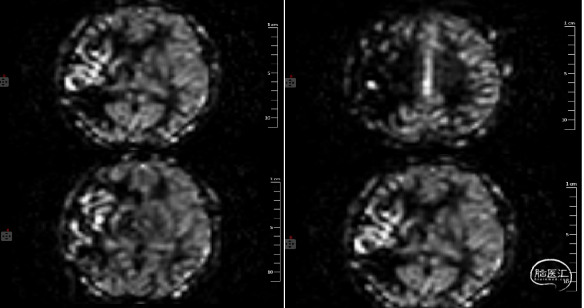

CTP:

DSA: